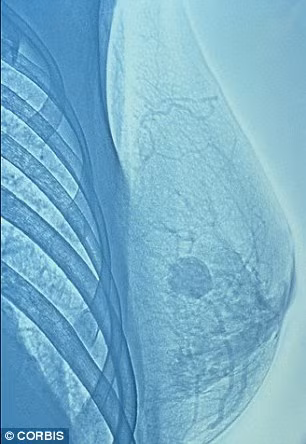

Việc có thể dự đoán và ngăn chặn bệnh ung thư vú là một thành tựu đáng kể của các nhà khoa học. Thường, bệnh ung thư vú có thể được phát hiện thông qua phương pháp nhũ ảnh, nhưng khi đó, các mô ung thư đã phát triển.

| Phương pháp nhũ ảnh giúp phát hiện ung thư vú, nhưng khi đó khối u ung thư đã phát triển. |

Đầu năm nay, các nhà khoa học thuộc Trường đại học Copenhagen của Đan Mạch đã phát triển một thí nghiệm cho phép phát hiện ung thư vú trước thời điểm phát tác từ 2 đến 5 năm. Và với thành tựu mới đạt được, các nhà khoa học Anh đã tiến được một bước dài trong công cuộc dụ đoán bệnh ung thư vú trước khi nó bùng phát.